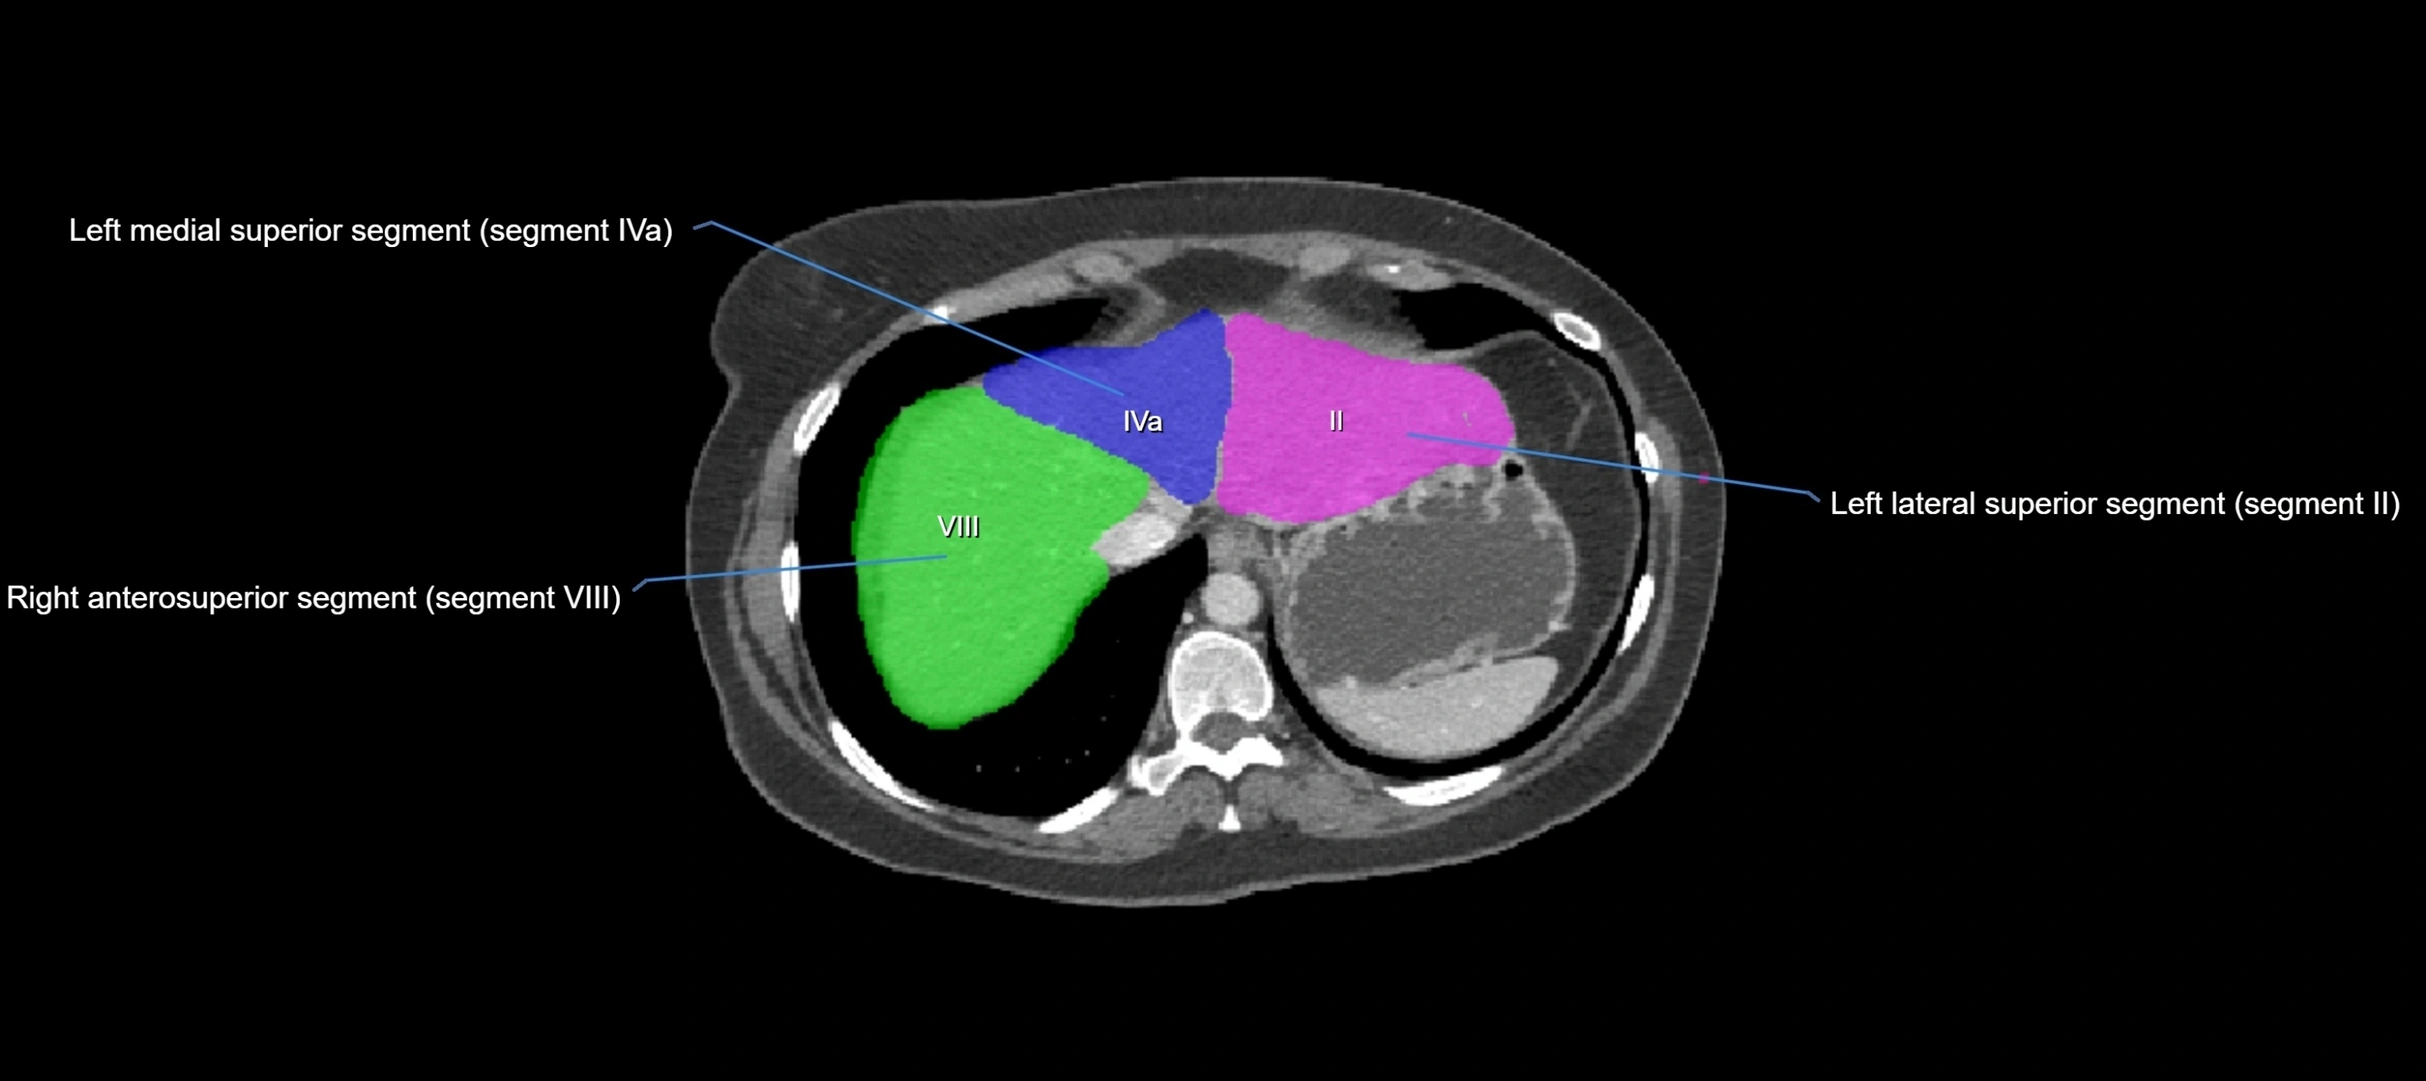

The caudate lobe of the liver is a distinct anatomical subdivision of the liver, designated as segment I in Couinaud’s classification. It lies on the posterior surface of the liver, between the fissure for the ligamentum venosum (left boundary) and the groove for the inferior vena cava (IVC) (right boundary). Superiorly, it is related to the posterior liver surface, and inferiorly it is separated from the left lobe by the porta hepatis.

image

CT Image